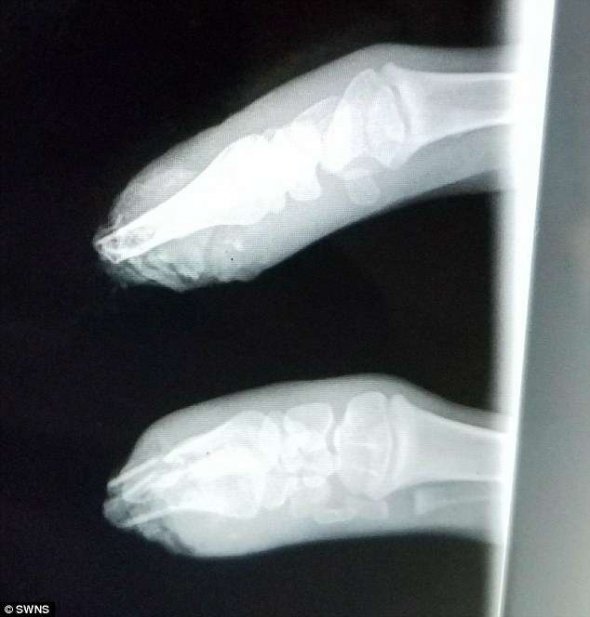

Через тиждень після народження козеня перенесло свою першу операцію. Там її кістки підрівняли, аби пізніше встановити на них протез. Три спроби зі встановлення протезу були невдалі. Лише остання, яку провели минулого тижня, закінчилася успіхом.

Miracle lost her front legs below the knee when her owner's pet Great Pyrenees chewed them off as they stuck out of her mother during birth. #Animal #Farm #PygmyGoat pic.twitter.com/uMn8dTO1HY